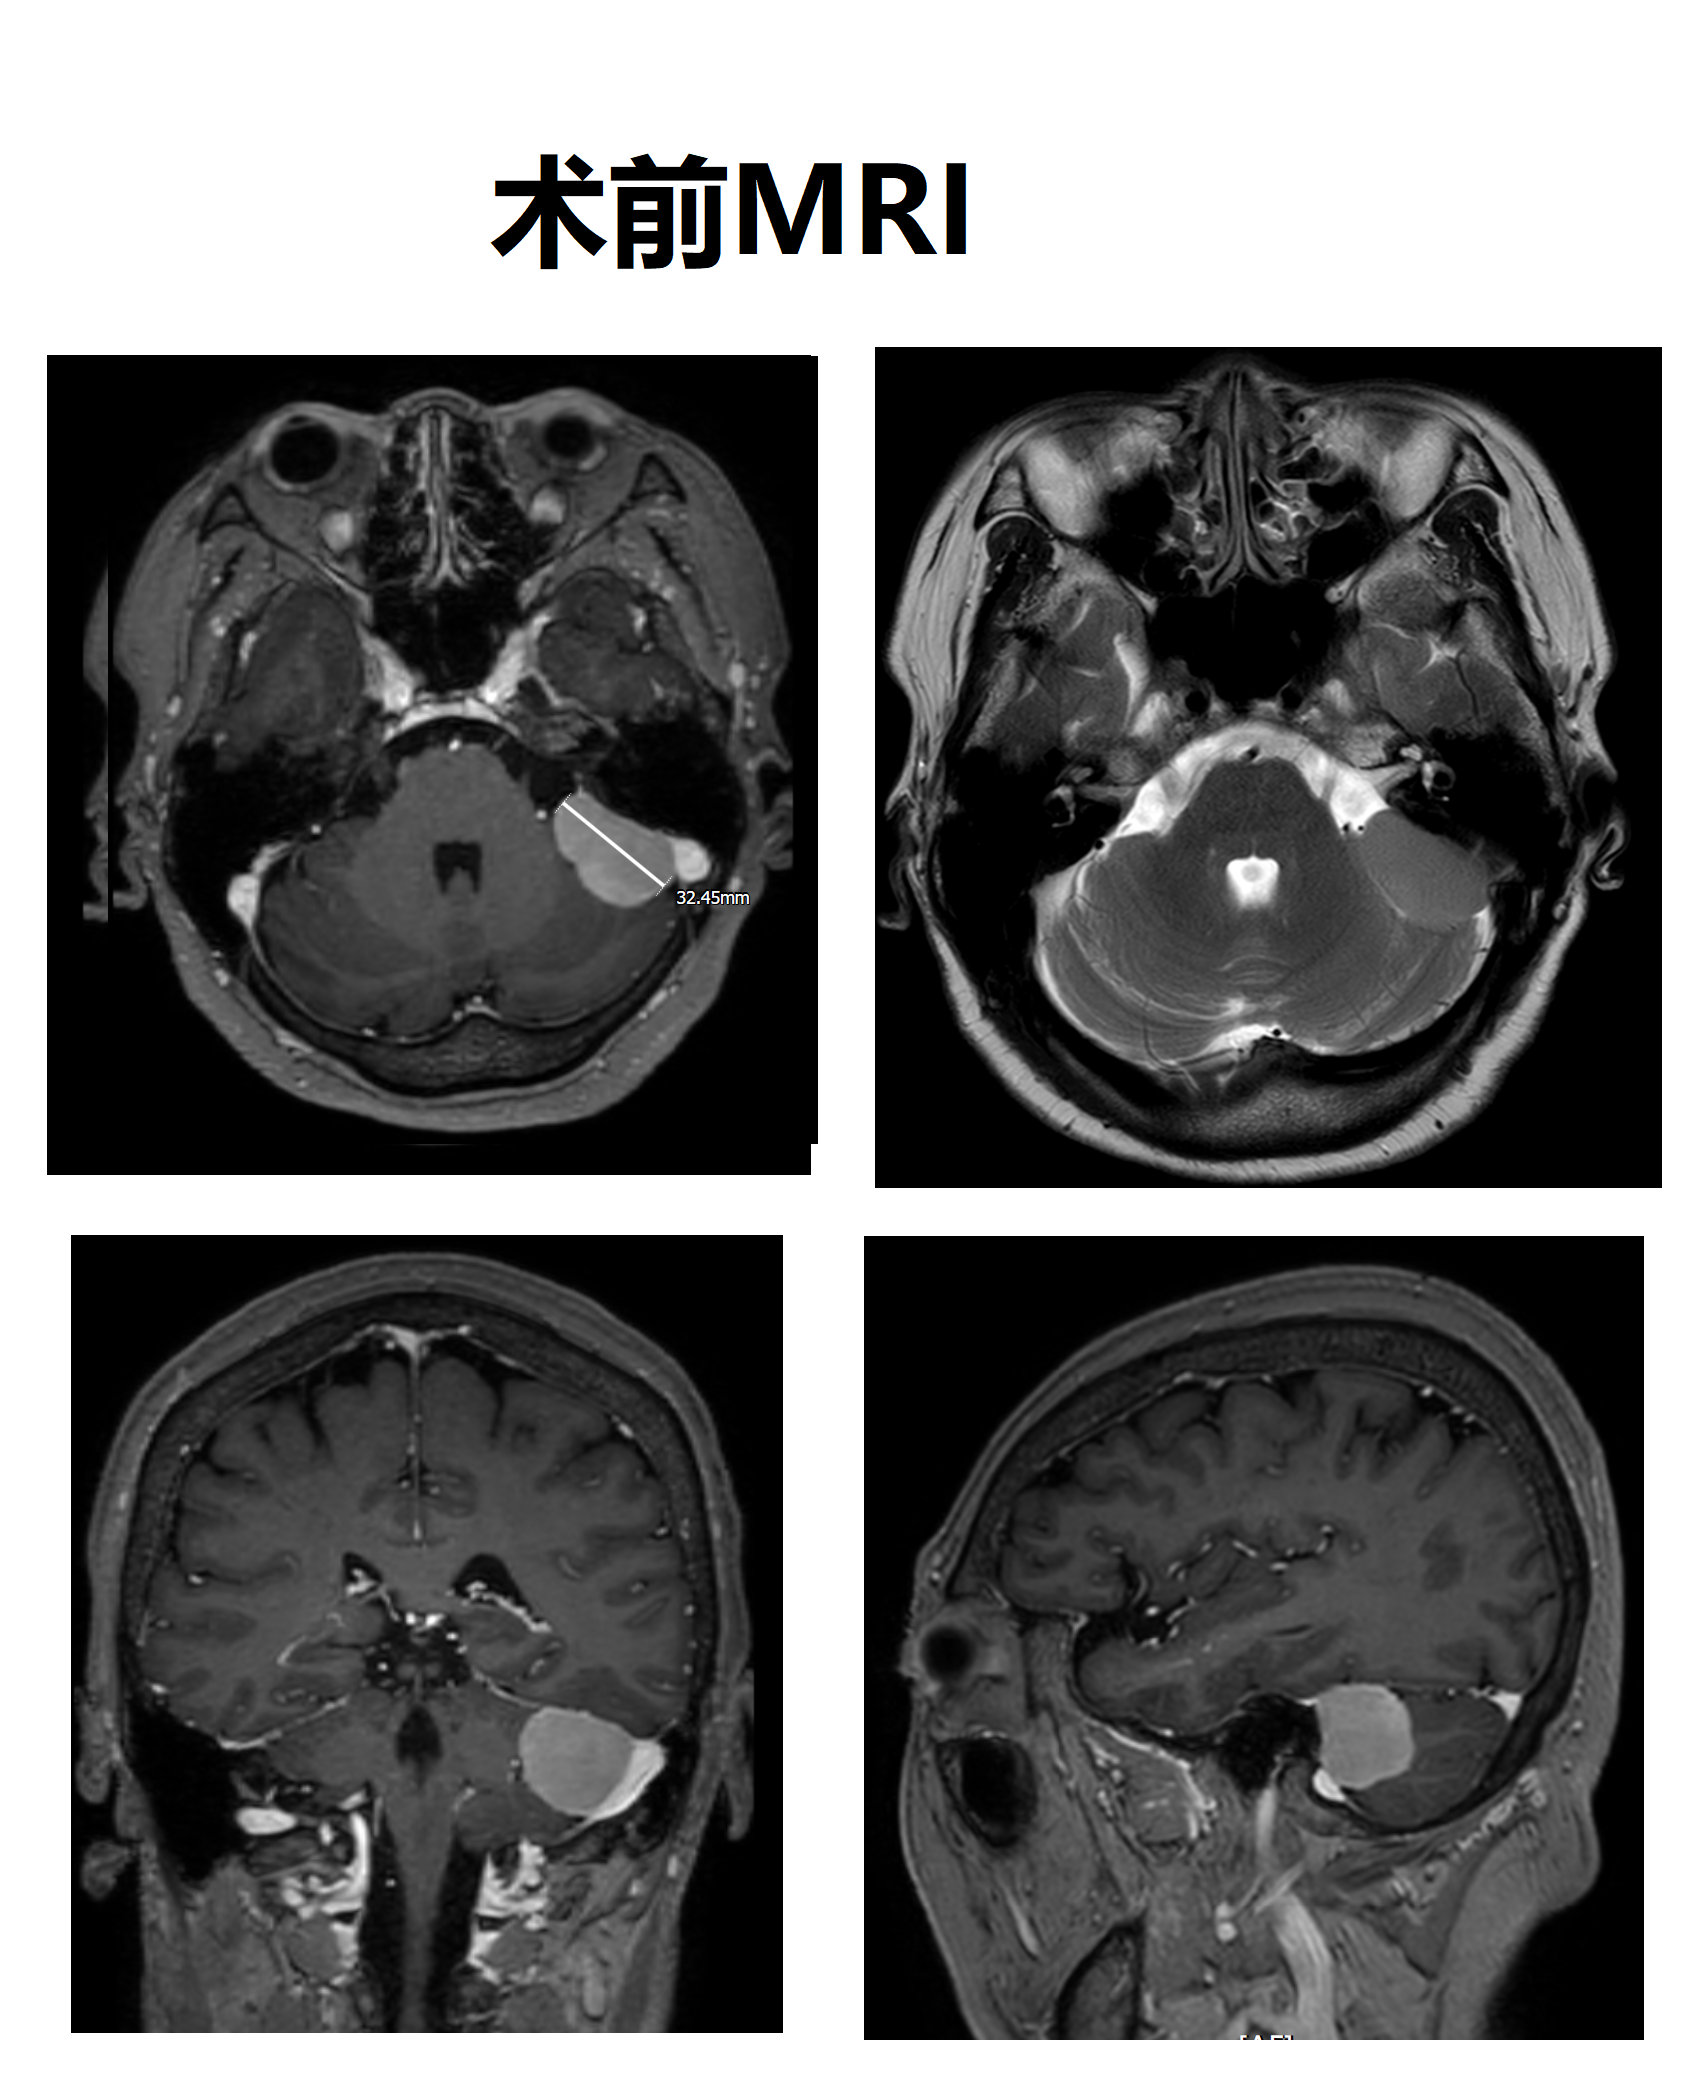

近日笔者完成一例左侧岩面/乙状窦旁脑膜瘤,最大径32mm,术前阅片见肿瘤与左侧乙状窦关系密切,与面听神经、后组颅神经有一定距离,手术相对安全。